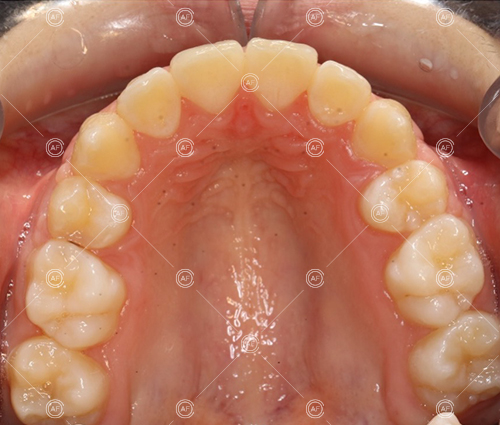

MH debonded in December 2020, with overall treatment time of around 14 months.

She was provided with upper and lower vacuum form retainers, and asked to wear these every night for the first year, and alternate nights for the second year onwards, indefinitely for as long as she wanted her teeth to remain straight. High quality finish was maintained at one year post-debond.